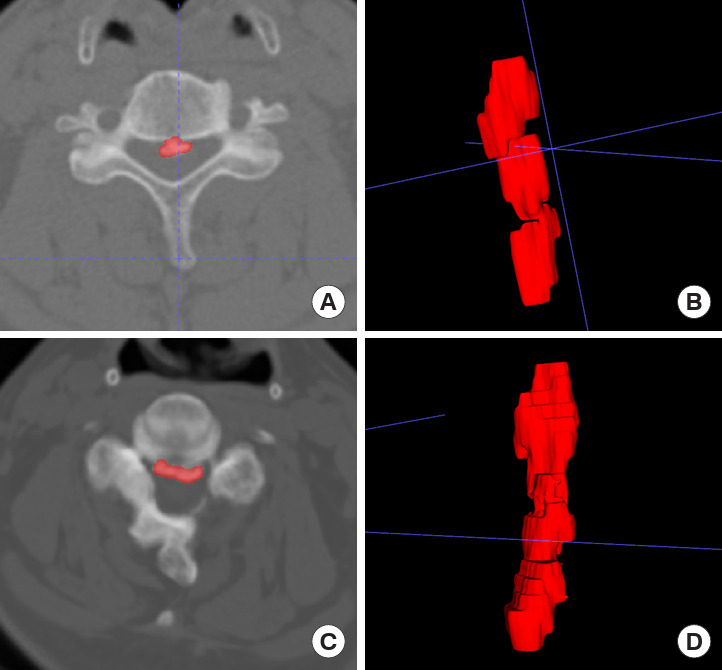

Methods: This retrospective study included 473 patients diagnosed with OPLL at Peking University Third Hospital between October 2006 and September 2022. Patients underwent posterior spinal surgery and had at least 2 computed tomography (CT) examinations spaced at least 1 year apart. OPLL progression was defined as an annual growth rate exceeding 7.5%. Radiomic features were extracted from preoperative CT images of the OPLL lesions, followed by feature selection using correlation coefficient analysis and least absolute shrinkage and selection operator, and dimensionality reduction using principal component analysis. Univariable analysis identified significant clinical variables for constructing the clinical model. Logistic regression models, including the Rad-score model, clinical model, and combined model, were developed to predict OPLL progression.

Abstract Image